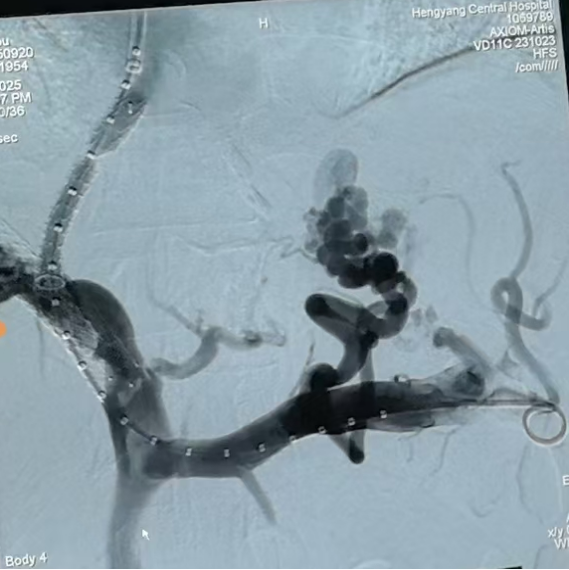

圖一:TIPS術(shù)中

第三步,手術(shù)實(shí)施與術(shù)后管理9月20日,在消化介入團(tuán)隊(duì)精湛操作下,成功為患者實(shí)施TIPS支架修補(bǔ)術(shù)。術(shù)中,團(tuán)隊(duì)克服了患者肝內(nèi)血管結(jié)構(gòu)因既往手術(shù)和肝硬化而異常復(fù)雜等諸多困難,精準(zhǔn)地在門靜脈與肝靜脈之間建立了有效分流,并置入覆膜支架以確保分流道長(zhǎng)期通暢。術(shù)后門靜脈壓力即刻顯著下降,達(dá)到了預(yù)期血流動(dòng)力學(xué)目標(biāo)。

圖二:TIPS術(shù)中影像